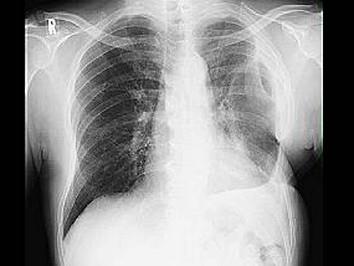

问题 如图,脓胸的病理改变,下列哪项不正确? ( )

选项 A、机化期形成纤维板易压迫肺组织的过程 B、脓胸病理改变的不同阶段有明显的界限 C、渗出期即脓胸急性期 D、纤维素化脓期是急性脓胸转变为慢性 E、脓胸主要是胸膜腔继发感染

答案 B